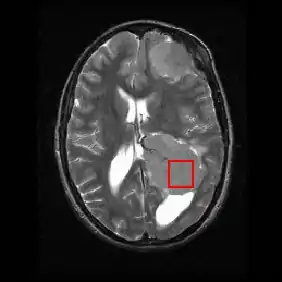

Shown below is an MRI brain scan (in the axial plane, that is slicing from front-to-back and side-to-side through the head) showing a brain tumor (meningioma) at the bottom right. The red box shows the volume of interest from which chemical information was obtained by MRS (a cube with 2 cm sides which produces a square when intersecting the 5 mm thick slice of the MRI scan).

Each biochemical, or metabolite, has a different peak in the spectrum which appears at a known frequency. The peaks corresponding to the amino acid alanine, are highlighted in red (at 1.4 ppm). This is an example of the kind of biochemical information which can help doctors to make their diagnosis. Other metabolites of note are choline (3.2 ppm) and creatine (3.0 ppm).